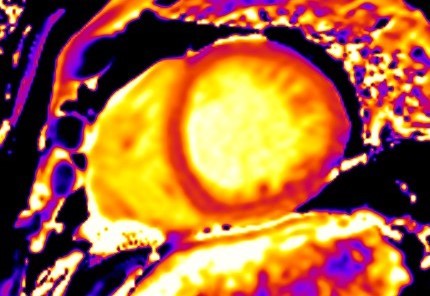

T1-weighted (T1-W) imaging is used for the anatomical assessment of the heart. Late gadolinium enhanced T1-W images (LGE), taken 8–15 min. After gadolinium-based contrast administration using inversion recovery pulse sequences, permit the detection and quantification of myocardial replacement fibrosis [11] (Fig. 5), if T2-W images in the same regions are negative.

Fig. 5.Replacement fibrosis evaluation using late gadolinium enhancement. Short axis with extensive late gadolinium enhancement (interventricular septum, anterior wall, inferior wall) in a patient with polymyositis and ventricular arrhythmias.